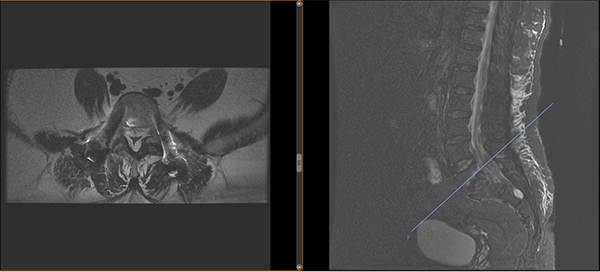

術(shù)后影像

手術(shù)很順利,脊柱外科在微創(chuàng)置釘技術(shù)下將滑脫完全復(fù)位,術(shù)后覃阿姨腰痛逐漸緩解,她對治療效果非常滿意,現(xiàn)已康復(fù)出院。